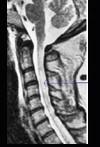

问题 患者,女性,23岁,11天前出现发热、头痛和全身酸痛,近两天出现颈背疼痛,四肢无力,查体四肢肌张力低,腱反射消失,病理征(-),C平面以下痛觉减退,尿潴留,行颈髓MRI T2加权像出现如图所示病变。最可能的诊断是 ( )

选项 A、脊髓肿瘤 B、格林—巴利综合征 C、急性脊髓灰质炎 D、急性脊髓炎 E、多发性神经病 一、单项选择题

答案 D